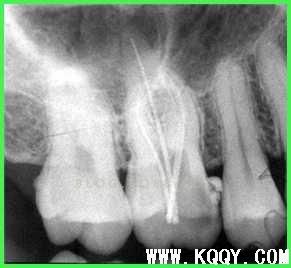

根管测量

1.摄片确定和根测仪相结合的方式进行。

2.当根测和插针摄片存在很大差距时需要谨慎!!!!什么原因?金属冠?金属充填物?侧穿?根裂?未干燥?

3.根测仪测试前要干燥根管。

4.在穿过根狭窄区时手上是有感觉的如果没有感觉建议:根测仪黄红交界时退0.5MM。